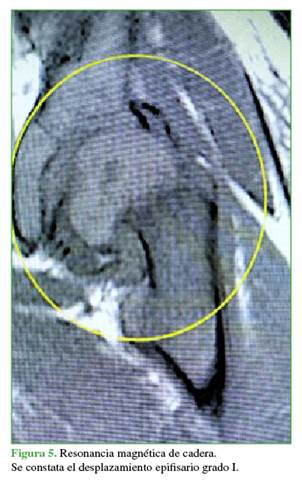

Se realizó una punción-aspiración con el paciente bajo anestesia para evaluar el grado de desplazamiento epifisario1 y evacuar el hematoma articular.2 Luego, con poco líquido de contraste, se efectúo una artrografía que constató el desplazamiento y su inestabilidad. La resonancia magnética es otro estudio para llegar al diagnóstico, si se duda de la inestabilidad, pero se debería contar con un resonador cerca o dentro del quirófano para realizarla en el mismo acto anestésico (Figuras 4 y 5).